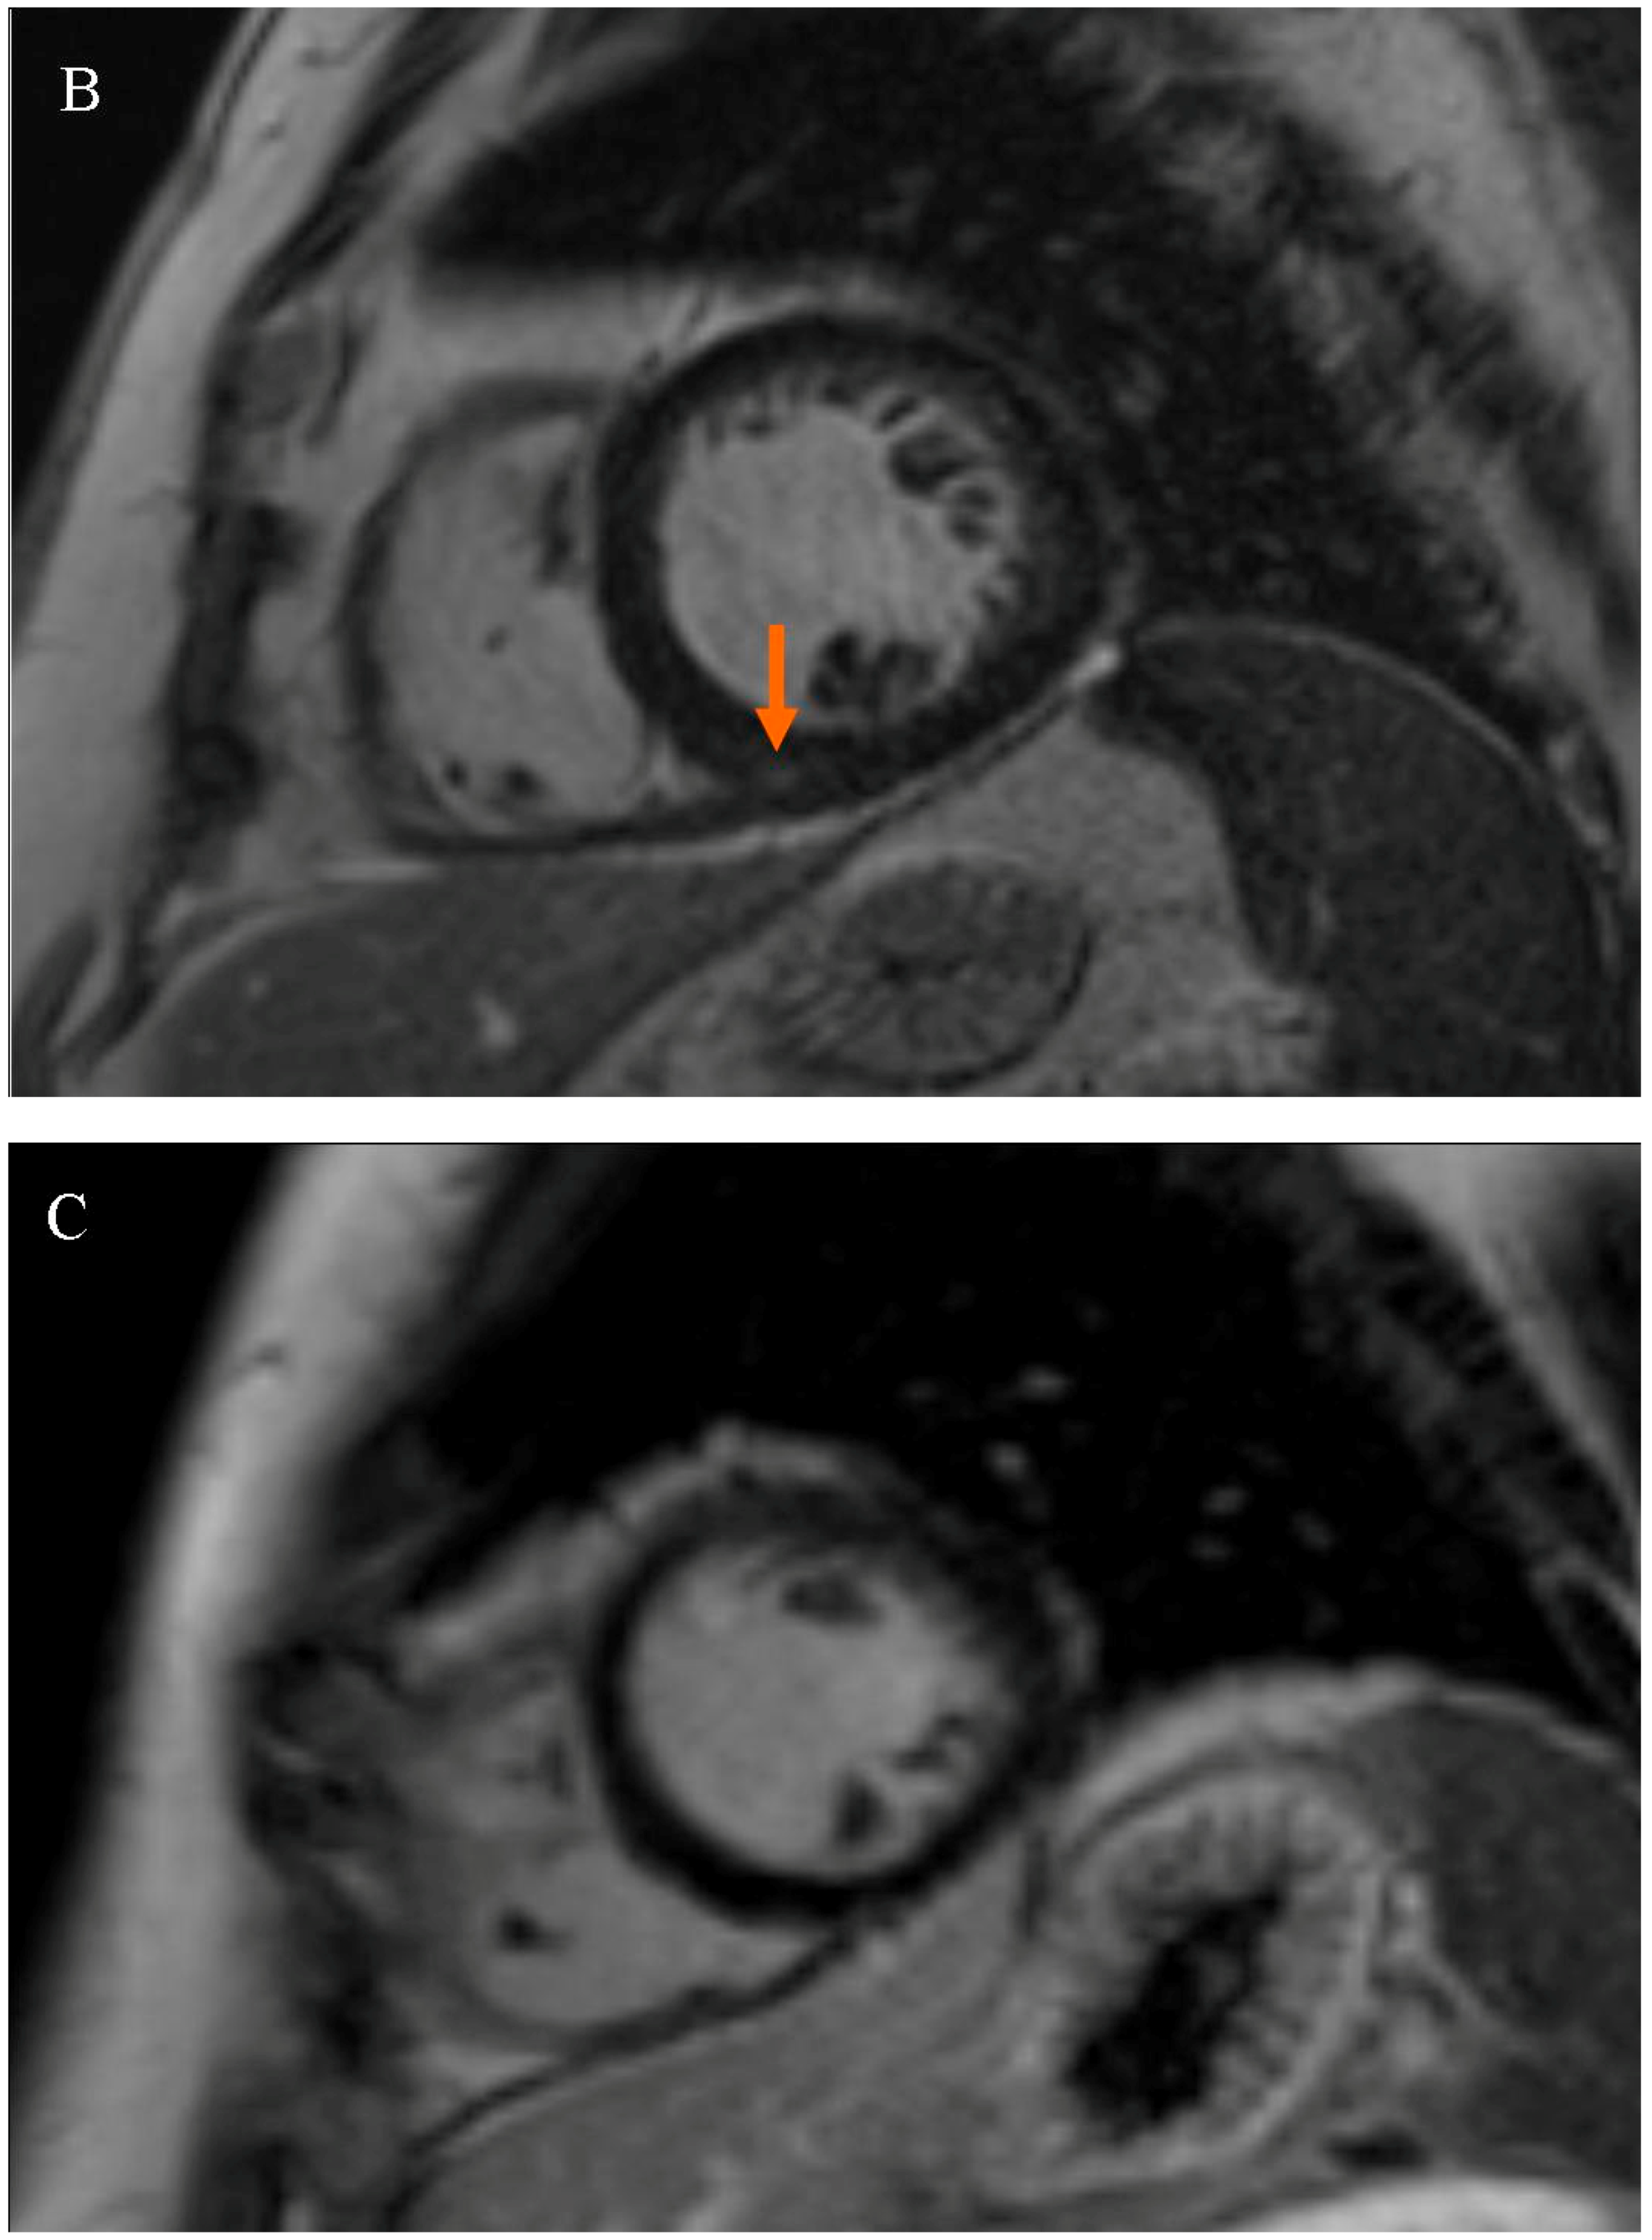

Patients were divided into two subgroups based on the presence of LGE at the RVIP. The first subgroup consisted of subjects with LGE at the right ventricular insertion point (RVIP+ subgroup), while the second subgroup consisted of subjects without LGE at the right ventricular insertion point (RVIP− subgroup), Figure 1.

Figure 1.

Late gadolinium enhancement (LGE) sequence images in cardiac magnetic resonance (CMR): (A) in a female patient with an LGE focus on the right ventricular insertion point (indicated by an orange arrow), (B) in a male patient with a subtle LGE focus on the right ventricular insertion point (indicated by an orange arrow), and (C) in a patient without LGE foci.